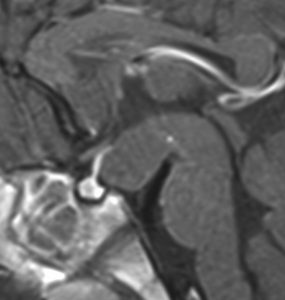

幼児期に思春期早発で発症

思春期早発で発症した幼児の視床下部過誤腫

視神経交叉の後方,乳頭体の前からぶら下がるようにしてあります

典型的な有茎状タイプです